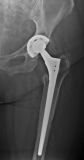

3. Periprosthetic fracture of the left femur in a 78-year- old female with a total hip arthroplasty.

Treatment: Revision of THA

I. Anteroposterior x-ray pelvis-hips shows the periprosthetic fracture. The patient referred to Mr. Papasotiriou Antonios one year after the periprosthetic fracture because of pain. The reason of pain was the loosening of the stem. II. Four months post-surgery anteroposterior x-ray left hip shows the revision of the femur stem with a new longer specific stem